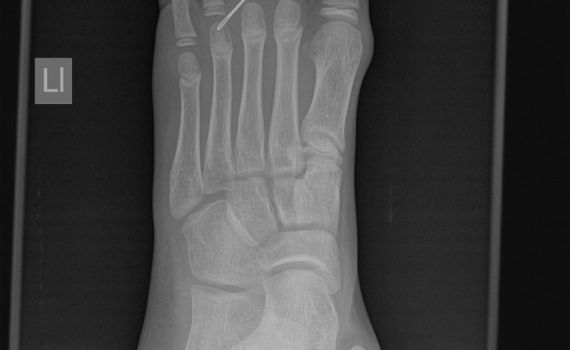

המחט חדרה לכף הרגל של הילד ונשברה צילום: צילום המסמר והרגל (באדיבות טרם)

למיון 'טרם' בבאר שבע הובהל ילד כבן 12, תושב האזור, כשהוא מתלונן על מחט שבורה הנעוצה בכף רגלו.

בתשאול שערכו אנשי הצוות הרפואי הסתבר כי הילד דרך על המחט והחל סובל מכאבים חזקים. כשהבין כי המחט חדרה לכף רגלו, ניסה הילד להוציאה באופן עצמאי אולם לדאבונו, נשברה המחט במהלך ניסיון ההוצאה, ולכן חש למיון.

אנשי הצוות הרפואי במיון 'טרם' ביצעו לאיש בדיקות מקיפות ובהם צילום רנטגן ובדקו את הפגיעה. לאחר שגילו כי לא נגרמו פגיעות בכלי דם ברגל, ביצע רופא 'טרם', תחת הרדמה מקומית, פעולה כירורגית להוצאת המחט, ובתום זמן קצר מאז פקד הילד את שערי המיון, הוא שוחרר לביתו בתום טיפול מסור ומקצועי.